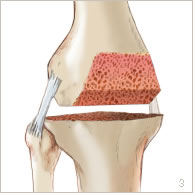

Une incision est réalisée au niveau de la partie antérieure du genou. Un passage est fait à la partie interne de la rotule pour accéder à l’articulation. Le cartilage usé est enlevé. Le fémur, le tibia et la rotule sont préparés pour recevoir la prothèse (figure 3).